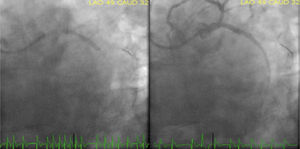

Case reportAn 84-year-old male patient with the cardiovascular risk factors obesity (body mass index 36 kg/m2), dyslipidaemia, arterial hypertension, type 2 diabetes mellitus, and a past medical history of permanent atrial fibrillation (AF) on anticoagulation with acenocoumarin, presented to our emergency department because of persistent oppressive chest pain and shortness of breath nine hours in duration. At admission, he was conscious (Glasgow Coma Scale 15) and symptomatic. On physical examination, he was normotensive (SAP∼118 mmHg) and normocardic (87 bpm), without signs of tissue hypoperfusion. Cardiac sounds were irregular on auscultation and he had an apical blowing holosystolic murmur, radiating to the axilla, grade IV/VI (Levine grading scale). Lung auscultation showed bilateral lower half rales. His electrocardiogram showed AF rhythm, with ST-segment elevation in leads II, III, aVF and ST-segment depression in leads V2-V4. Acknowledged inferoposterior acute myocardial infarction and a loading dose of 600 mg clopidogrel, 300 mg acetylsalicylic acid and an IV bolus dose of unfractionated heparin (5000 IU) were given. The patient was immediately referred for primary percutaneous coronary intervention (PCI). As we can see in Figure 1, emergent coronary angiography (CAG) revealed a dominant left coronary artery, showing total occlusion of the proximal segment of left circumflex artery (LCX) and a moderate lesion (40%) in the proximal left anterior descending artery. Right coronary artery was a small vessel with diffuse irregularities. Because of high thrombotic burden, we performed manual thrombus aspiration of LCX as an initial strategy using a 6 Fr aspiration catheter with multiple passages across the lesion. Thereafter, CAG revealed Thrombolysis in Myocardial Infarction (TIMI) 3 flow in the culprit vessel. A protection guidewire was advanced to the left obtuse marginal artery and we performed a PCI of LCX proximal lesion with deployment of a 4.0×24 mm everolimus-eluting stent (Synergy). The procedure was complicated by no reflow phenomenon after stent implantation, with slow spontaneous improvement until a final TIMI 2 flow in the LCX artery (Figure 2).